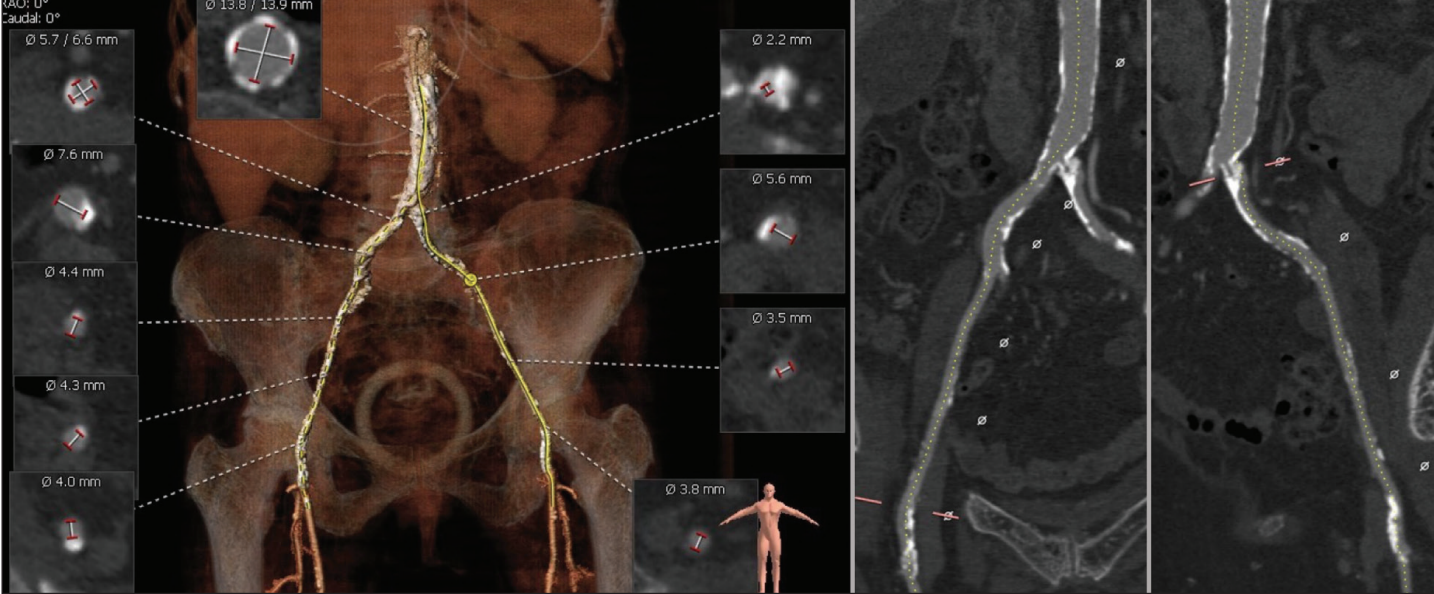

The abdominal aorta had extensive calcification with a longest calcium gap of 4.5 mm in the aortic wall adjacent to the inferior vena cava. The iliofemoral vessels were severely narrowed and heavily calcified with minimum diameters of 2.2 mm in the left common iliac and 4 mm in the right common femoral arteries (Figure 4). The minimum subclavian diameter was 4.3 mm. The aortic root was relatively free of calcium (Figure 5).